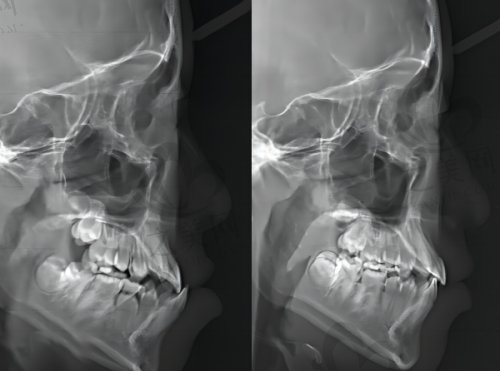

山西阳泉庆鸿口腔是当地的高人气口腔诊疗机构,作为该地区口腔保健领域的佼佼者,以其可靠的服务和新型的技术吸引了众多患者的青睐。这里拥有一支团队,团队成员均具备扎实的专科知识和一定的临床经验,能够为患者提供个性化的口腔诊疗方案,无论是常规的洁牙、牙齿矫正等都能胜任。